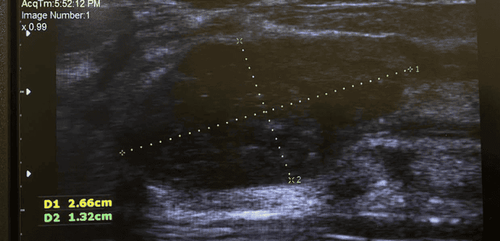

At Vinmec Times City International General Hospital, the patient was examined and found to have severe internal tibial torsion, along with other abnormalities. The deformity had an internal angle of 51.4 degrees in relation to the joint surface, a leg length discrepancy of 4 cm, pelvic tilt, scoliosis, thigh muscle atrophy, and ankle joint involvement, including deformation and degeneration of the ankle joint.

After calculating the surgical plan on the computer, the patient's bone model was 3D printed for experimental surgery. After the success of the experiment, a personalized 3D-printed surgical guide was used in the surgery, allowing the surgeon to make precise bone cuts as planned, resulting in a smooth, complication-free surgery.

"In this case, the patient’s deformity was complex, involving large degrees of misalignment in multiple planes, not only evaluating the severity of the deformity but also developing surgical plan and ensuring its accuracy, is very challenging, However, this challenge was solved by using the 3D-printed personalized surgical guide," explained Professor Tran Trung Dung.

The purpose of this guide is to connect the information about the deformity with the surgical plan calculated on the software, making the surgery as precise as possible.